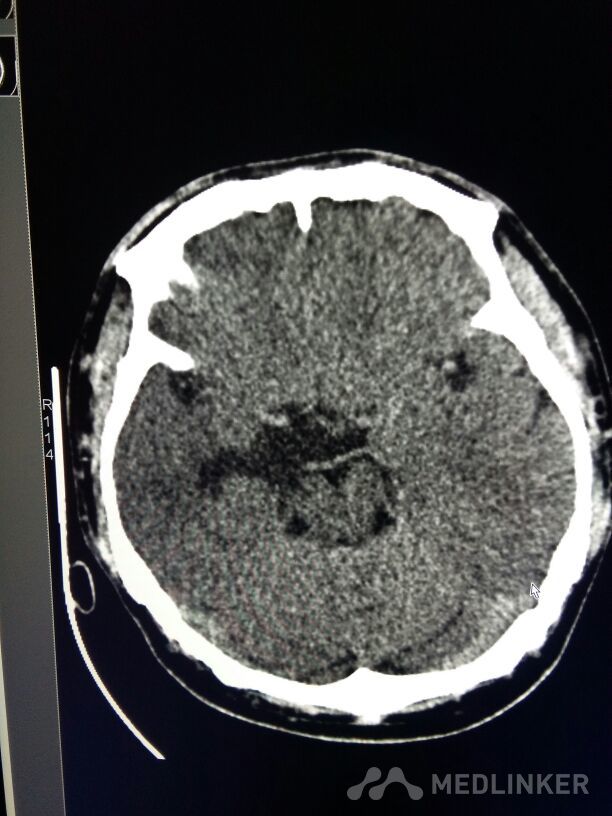

考虑表皮样囊肿?

表皮样囊肿